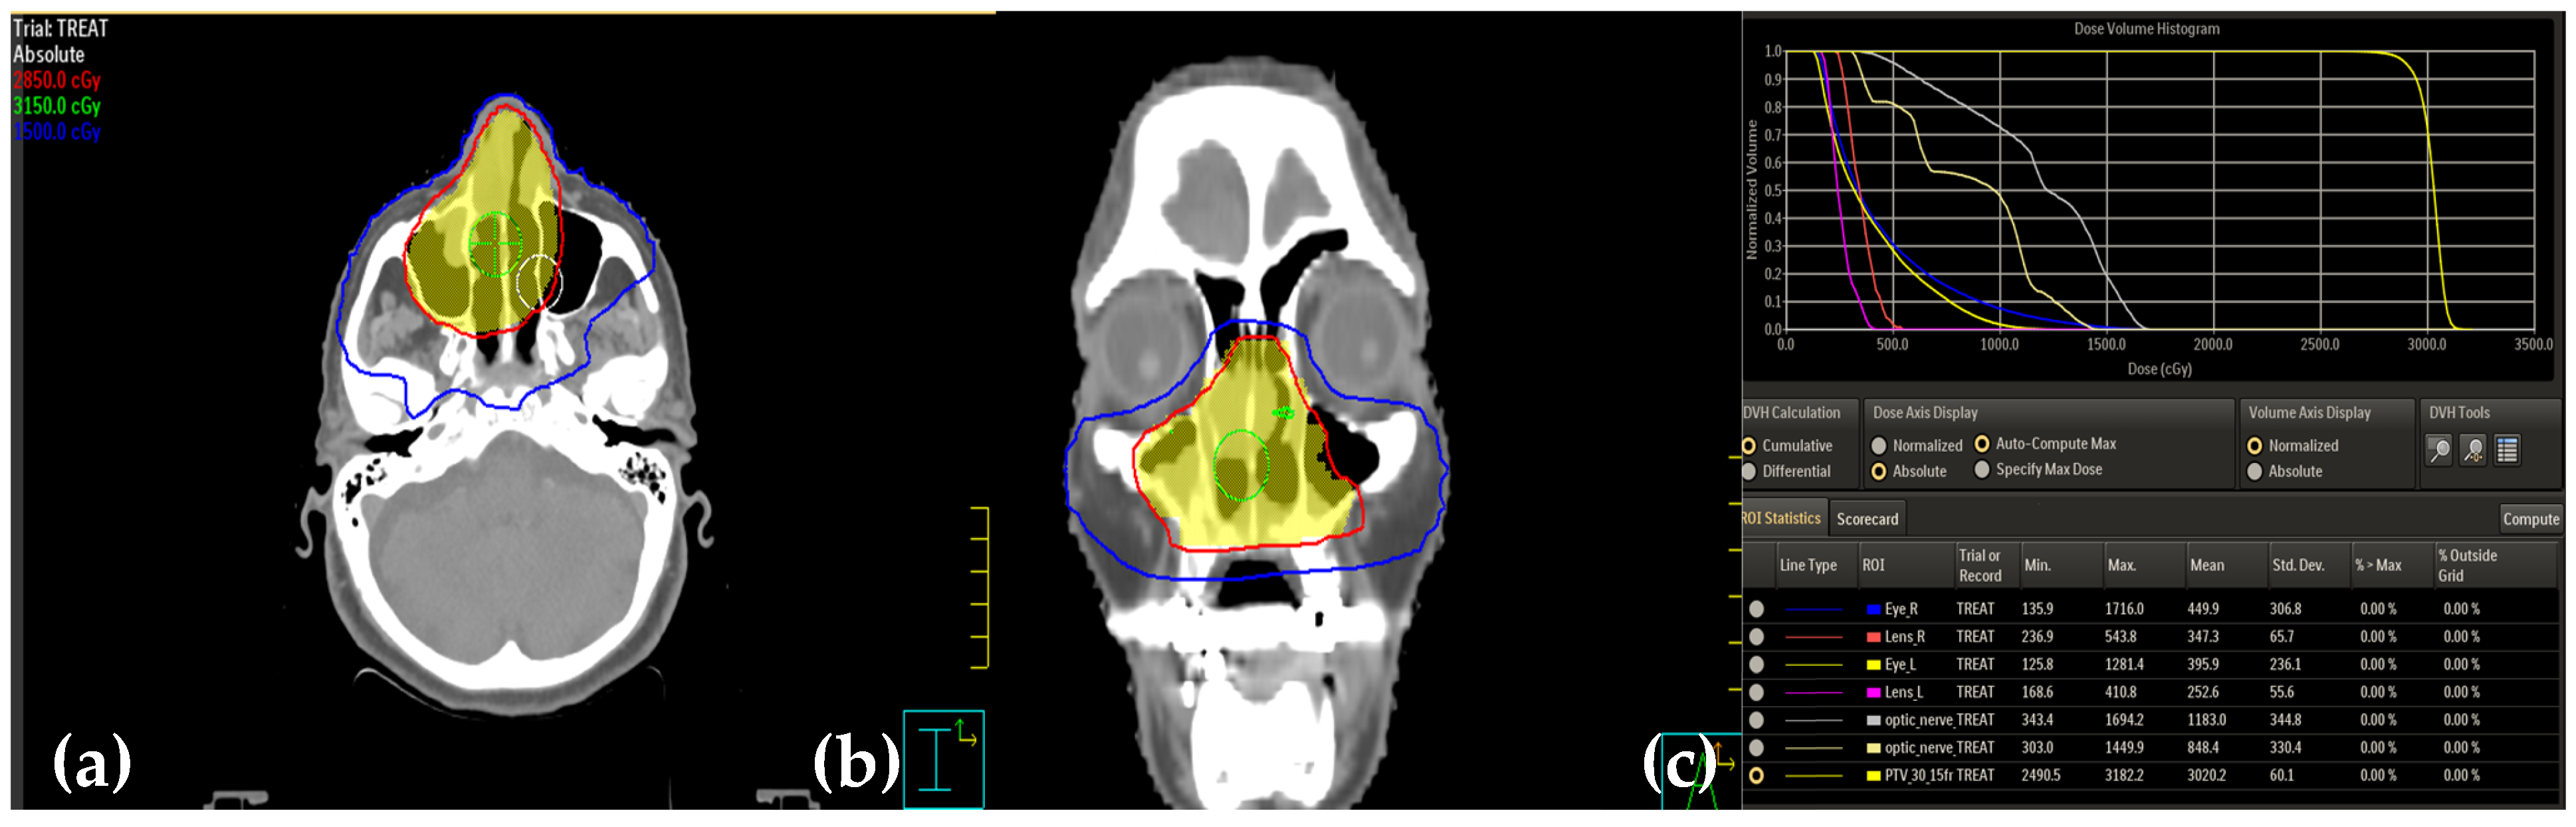

2. Case Presentation